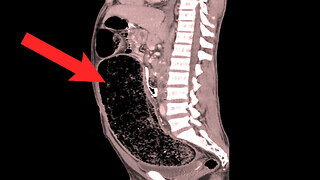

Chubbyemu

10 days agoA Lawyer Couldn't Sleep For 9 Days. This Is What Happened To Her Colon.

1.02K9 -